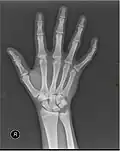

In human anatomy, the metacarpal bones or metacarpus, also known as the "palm bones", are the appendicular bones that form the intermediate part of the hand between the phalanges (fingers) and the carpal bones (wrist bones), which articulate with the forearm. The metacarpal bones are homologous to the metatarsal bones in the foot.

The metacarpals form a transverse arch to which the rigid row of distal carpal bones are fixed. The peripheral metacarpals (those of the thumb and little finger) form the sides of the cup of the palmar gutter and as they are brought together they deepen this concavity. The index metacarpal is the most firmly fixed, while the thumb metacarpal articulates with the trapezium and acts independently from the others. The middle metacarpals are tightly united to the carpus by intrinsic interlocking bone elements at their bases. The ring metacarpal is somewhat more mobile while the fifth metacarpal is semi-independent.[1]

Each metacarpal bone consists of a body or shaft, and two extremities; the head at the distal or digital end (near the fingers), and the base at the proximal or carpal end (close to the wrist).